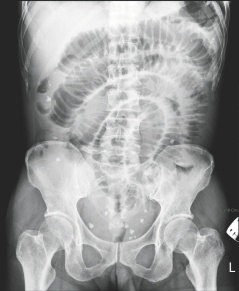

臺南市55歲女子腹中取出29顆大大小小的“蛋”,從X光上可看到腹中滿布點狀的白色物體。

這名女子最近因腹痛、嘔吐而到成大急診就醫,醫師從X光檢查中,發現腹腔內有許多白點狀的物體,原本以為是糞石或食物堆積在腸道中,經緊急開刀,發現這些物體是在腸子外,而非腸子里,醫師共取出大大小小共29顆,色白、外形橢圓,很像蛋一般,材質卻像橡膠一般有彈性。